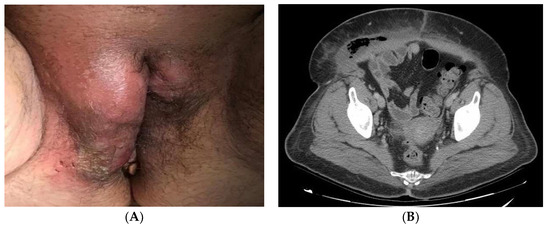

According to the initial evaluation, the patient was febrile (39 °C), tachycardic (123 beats/min), with blood pressure of 146/78 mmHg and respiratory rate of 22 breaths/min. The examination revealed a huge phlegmonous abscess on the right labia majora that extended to the mons pubis (Figure 1A). Rest of the examination was unremarkable. Laboratory workup revealed blood glucose of 243 mg/dL, mild leukocytosis (16,450/L) with 80% neutrophils and C-reactive protein (RCP) of 492 mg/dL. Normal coagulation times. No more unaltered parameters. A CT of the abdomen and pelvis revealed important inflammatory changes and air inside the soft tissues of the genital area extending to the right iliac and paraumbilical fossa compatible with FG (Figure 1B).

Figure 1.

(A): Perineal abscess with induration of surrounding tissue. The most common onset site of FG is the labia majora. (B): CT of the abdomen and pelvis showing areas with gas revealing necrotic tissue from gangrene.

On the initial scan, her general condition was fair. She had blood pressure around 122/52 mmHg, HR 110 bpm and 36 °C of temperature. Right labia majora was enlarged, indurated and erythematous. Additionally, she had a painful ulcer in the lower third. Blood tests revealed hemoglobin 8.9 g/dl, platelets 426,000/L, leukocytosis 37,640/L with 90% neutrophils and RCP of 285 mg/dl. Glycemia at 465 mg/dl. No more unaltered parameters were associated. A CT of the abdomen and pelvis showed subcutaneous edema and air in the perineal area and right vulvar area extending into the presacral soft tissues suggestive of FG (Figure 3).

Figure 3.

CT of the abdomen and pelvis showed subcutaneous edema and air inside the soft tissues of the genital area extending into the presacral soft tissues of FG. The hip replacement slightly distorts the image.